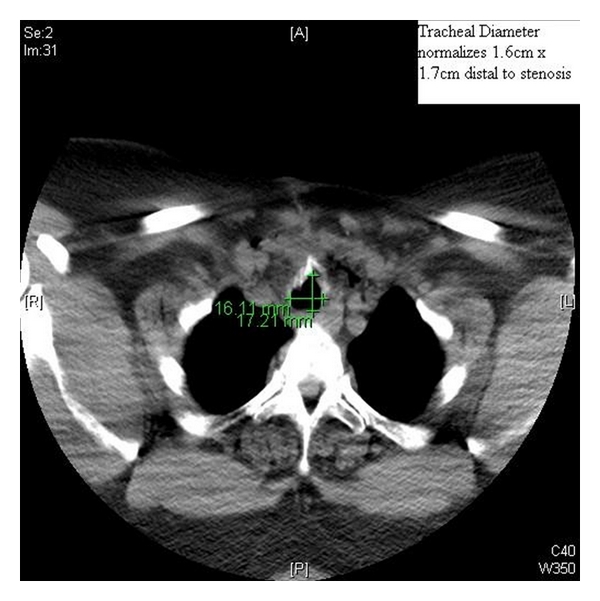

A 45-year-old woman with a long history of tracheal stenosis and upper airway obstruction presented for elective tracheostomy placement in the setting of supra- and infraglottic stenosis after failed awake tracheostomy by an otorhinolaryngologist (ORL) (Figures 1 and 2). It was felt by the attending ORL surgeon that the airway could not be secured from above after serial diagnostic scopes. Due to the failed awake tracheostomy, it was felt that surgical airway under bypass was the only option.